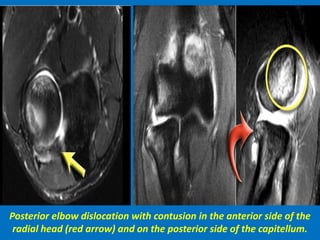

Coronal view: Lateral collateral ligament is completely stripped (yellow arrow).

radial head is subluxed. marrow edema of the coronoid process due to the

fracture (red arrow).

Sagittal view: Radial head is a little bit subluxed posteriorly (yellow arrow).

Large effusion and capsular disruption posteriorly. Contusion of the posterior side

of the capitellum as a result of impaction by the coronoid process (red arrow).

Posterior elbow dislocation with contusion in the anterior side of the

radial head (red arrow) and on the posterior side of the capitellum.